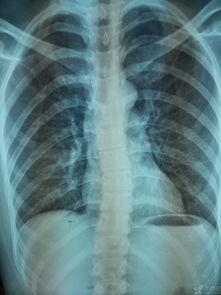

你知道吗,脊柱可是我们身体的支柱,它不仅支撑着我们的身体,还保护着脊髓。但是,随着生活节奏的加快,很多人都会出现脊柱问题,比如颈椎病、腰椎间盘突出等。这些问题的出现,不仅会影响我们的生活质量,还可能引发其他健康问题。所以,学会一些脊柱调理手法,真的是非常有必要的!